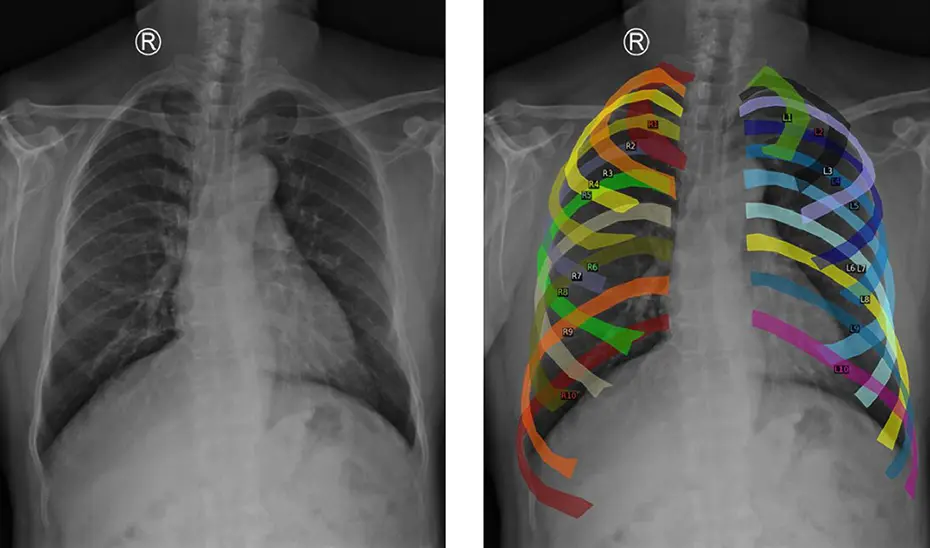

Para una mejora en el entrenamiento del modelo, se han empleado datos de distintos centros hospitalarios y una estrategia conocida como aumento de datos, en las que se segmentan las costillas y se alinean puntos clave del tórax para generar nuevas imágenes homogéneas desde una perspectiva anatómica. Con esto, se consigue que sea robusto, incluso ante radiografías de distintos hospitales, de diferente resolución o adquiridas con otro equipamiento. El sistema aprende mejor y funciona de forma más generalizada.